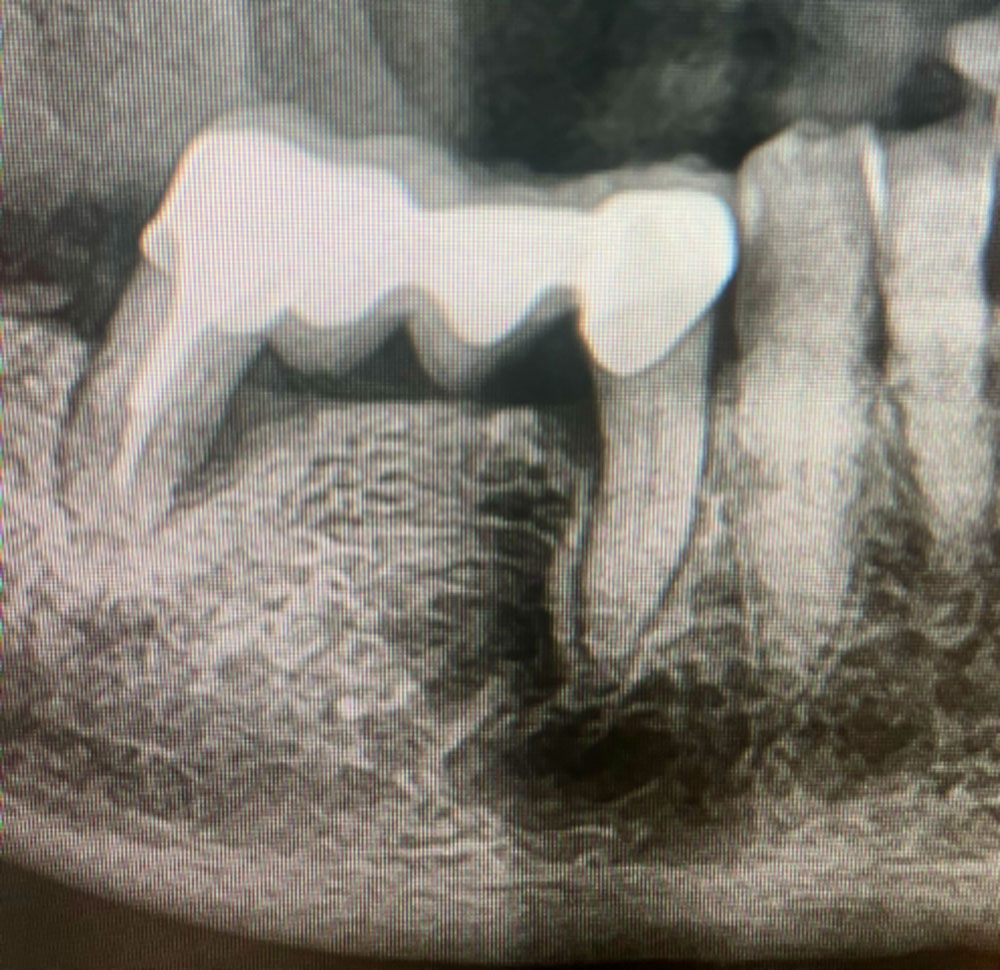

Dans ce cas clinique, la patiente de 72 ans présentait une dent support de bridge non conservable.

Après analyse clinique et radiologique, une extraction atraumatique suivie d’une implantation immédiate a été réalisée.